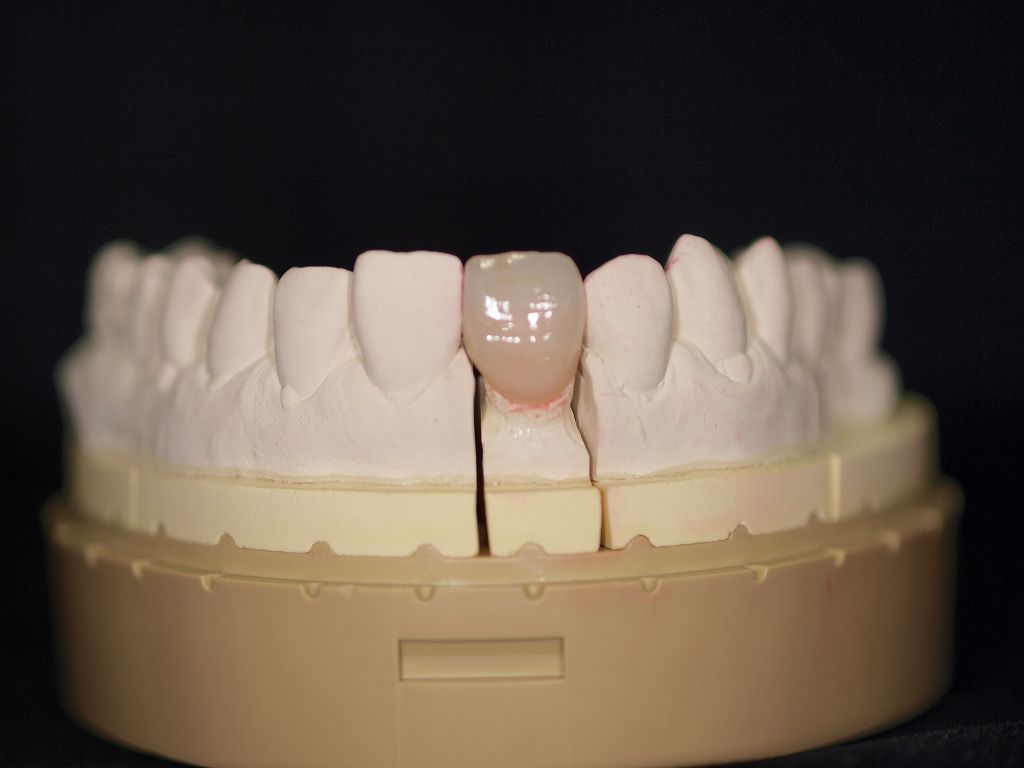

前歯部のセラミッククラウンにはジルコニアクラウンとオールセラミッククラウンの2通りが存在します。 オールセラミッククラウンはe-maxといわれるイボクラ社のガラス系二ケイサンリチウムをフレームとして使用していき、レイヤリングの形態をとります。|お知らせ |広島市安佐南区の歯科医院

前歯部のセラミッククラウンにはジルコニアクラウンとオールセラミッククラウンの2通りが存在します。 オールセラミッククラウンはe-maxといわれるイボクラ社のガラス系二ケイサンリチウムをフレームとして使用していき、レイヤリングの形態をとります。

前歯部のセラミッククラウンにはジルコニアクラウンとオールセラミッククラウンの2通りが存在します。 オールセラミッククラウンはe-maxといわれるイボクラ社のガラス系二ケイサンリチウムをフレームとして使用していき、レイヤリングの形態をとります。